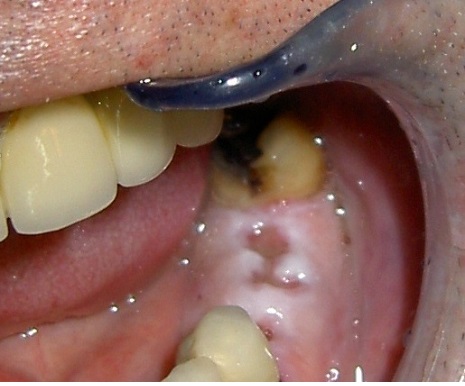

Ejemplo Implantes